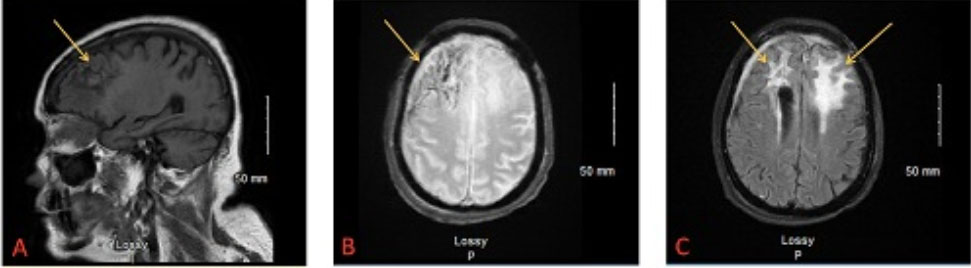

One month after being discharged for right eye blindness (six months after initial diagnosis), the patient followed up outpatient for a subsequent postoperative MRI. This imaging showed overall stable postoperative findings, however noted improvement in some regions and worsening in others. Her right frontal lobe abscess, first noted on CT six months prior, and paranasal sinus infection had improved dramatically. Nodular enhancement in the periphery of the left frontal lobe still persisted while left frontal lobe vasogenic edema had increased. In addition, there was notable dural and subdural thickening over the right frontal convexity. This increased concern for progression of the abscess (Figure 2A, Figure 2B, Figure 2C).

Figure 2: (A) T1 MRI image in sagittal plane, six months post-resection/craniotomy and initial diagnosis. Arrow denotes right front lobe abscess reduction from initial CT scan. (B) Gradient recalled echo (GRE) T2-weighted MRI image in transverse plane, six months post-resection. Arrow denotes reduction in right frontal lobe abscess. (C) Flair T2-weighted MRI image in transverse plane, six months post-resection. Arrows denote the nodular enhancement in periphery of left frontal lobe, persisting from original CT scan, and notable dural/subdural thickening over right frontal convexity. Concern for progression of abscess.